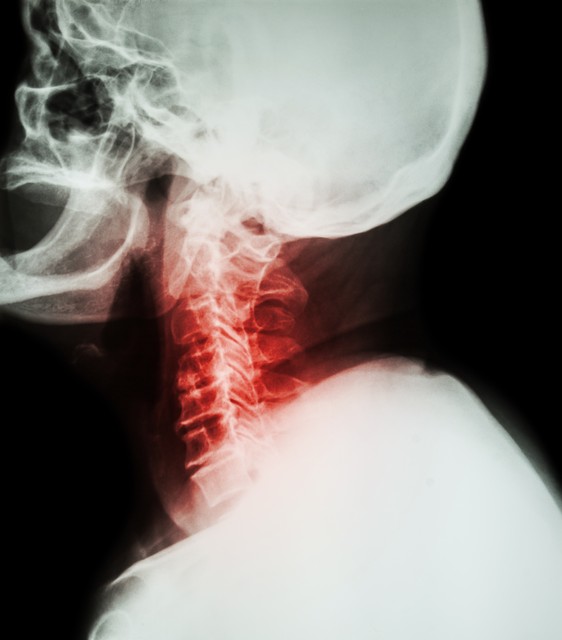

昨天上午出门诊时,有位患者上来就问了我一句:“医生,颈椎病有可能导致瘫痪吗?”我当时条件反射般地给出了肯定的答复。

颈椎病确实可能导致瘫痪,这是毋庸置疑的,最多只是几率大小的问题,跟绝大多数普通人不同,任何有医疗常识的医护人员都不会小瞧颈椎病,颈椎病虽然常见但绝不是小事,其临床分类较多、较为复杂。

就像我上文所说,颈椎病的临床分型很复杂,不同类型的颈椎病患者,不仅治疗方案不同,评估风险也有很大区别。

可以导致瘫痪的颈椎病,是什么样的?